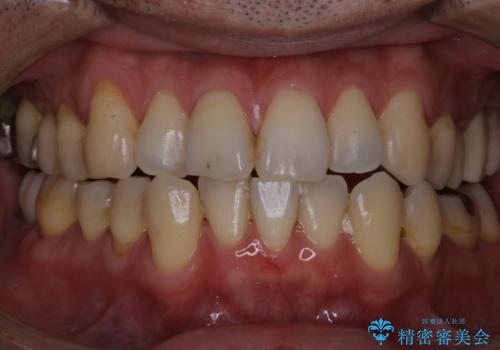

歯周病の治療前にまずはモチベーションUPにPMTCでステインの除去

担当医 歯科衛生士